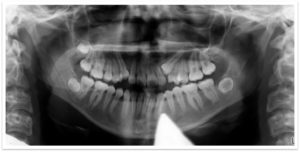

A 15 year old African American female presents with a chief concern that “I want to fix my canine and underbite”